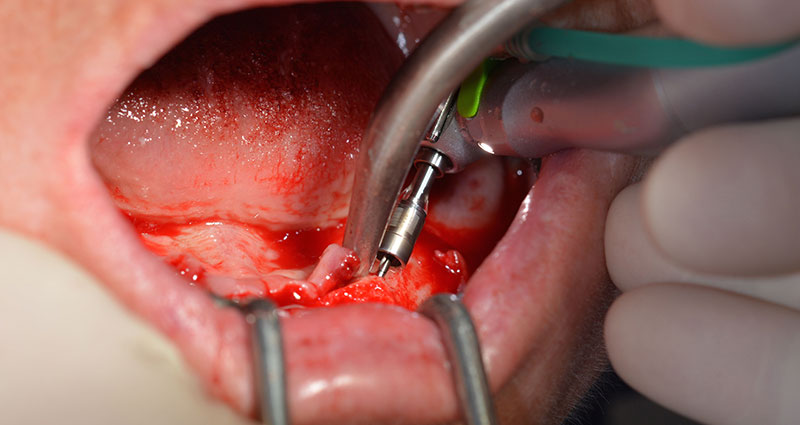

Le protocole chirurgical préconisé pour les implants utilisés (SKY, Bredent Medical) précise une vitesse de rotation de 1.200 tr./min. pour le pré-forage (Fig. 7 - 9).